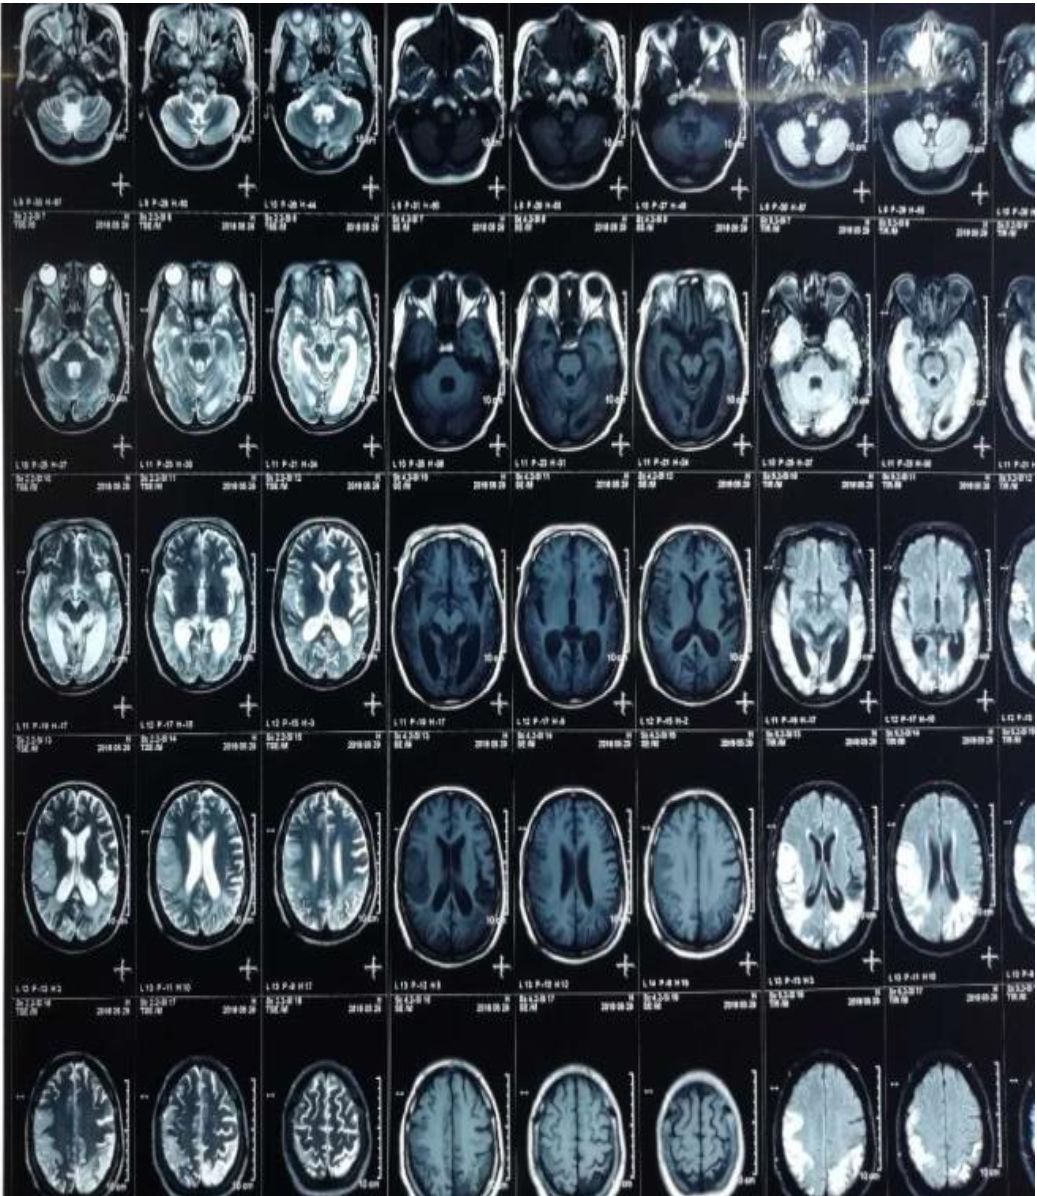

病例7

52岁,男性,头晕20余天,伴言语不利、智能下降。患者自述于20余天前无明显诱因下出现头晕,呈持续性头重脚轻感,无明显规律,伴有言语欠流利、智能下降,表现为计算力、理解力、记忆力下降,偶有咳嗽、呈阵发性单声咳,咳少许白色粘痰;间断发热,最高体温38.5℃。影像学如下:

影像学可见双侧颞、顶叶及右侧额叶多发散在皮层下白质病变,长T2,DWI高信号,ADC高信号。疾控中心HIV-1抗体:阳性,CD4+64cell/ul。

诊断: HIV相关脑病(HIV相关痴呆)

脑部 MRI 显示萎缩和广泛白质改变。运动障碍也可单独发生或伴随 HIV引起的痴呆一同发生发展。HIV 感染者中运动障碍的发生率为 3%。

其影像学表现常位于白质,如脑室旁、半卵圆中心,呈对称、弥漫、云雾样白质异常,病灶可延伸至灰白质交界处。